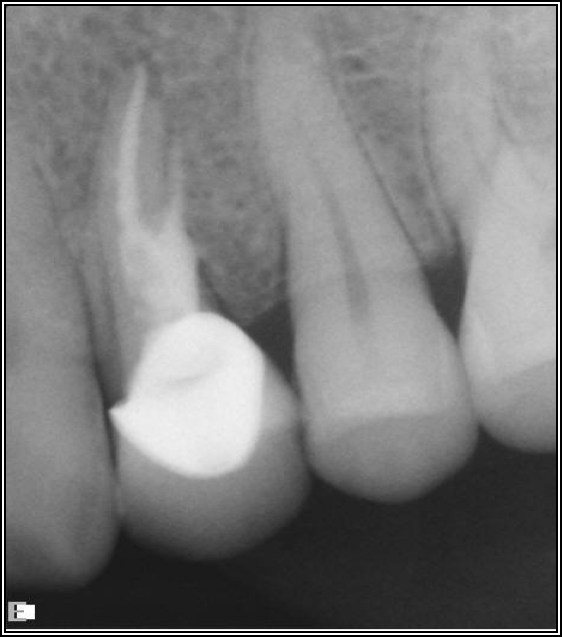

Fig 17. A case with a good fiber post on the lateral that could be longer.

Figure 17

As to which material to use, the literature indicates fiber is better because it has greater flexibility and is less likely to allow for vertical fractures.2,3 It also has better esthetics, which is significant for both anterior and posterior teeth. The problem with fiber posts is that they can snap off and pull out. When they snap off, they are difficult to remove. A tapered diamond bur or ultrasonic can be used, but it must be done very carefully. Depending on the circumstances, metal can also be difficult, but metal is often serrated or threaded and can be unwound with an ultrasonic. However, fiber is significantly more flexible because it has a better modulus of elasticity, which should be as close to the dentin's elasticity as possible. On the radiograph, it can be difficult to see. Figure 17 shows a case with a good fiber post on the lateral that could be longer. The central should definitely be longer than it is. Because the clinician thought the posts and crowns were well done with good seals, when the patient had pain and apical radiolucencies, they were treated with apicoectomies. This was easier and less invasive than dismantling the previous structure.